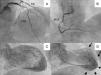

We present the case of a 70-year-old patient who went to the emergency department with chest pain and lateral ST elevation on the electrocardiogram. An emergent cardiac catheterization was performed, which showed epicardial arteries without significant angiographic lesions, and left ventriculography, which revealed extensive akinesia of the apex with mild systolic dysfunction (Figure 1).

(A) Cranial projection showing left anterior descending (LAD) and circumflex (CX) arteries without significant lesions; (B) cranial projection showing right coronary artery (RCA) without significant lesions; (C) ventriculography with left ventricle in end-diastole; (D) ventriculography showing left ventricle in end-systole, with apical akinesia (arrows).